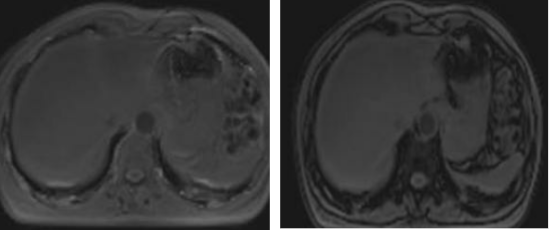

近日,玉溪市中山医院医学影像科在中山大学第一附属医院驻岗专家张朝晖教授指导下,利用联影uMR880 3.0T磁共振成功完成数例肝脏脂肪定量分析,帮助患者排除肝脏脂肪健康隐患。

磁共振检查主要为波谱检查和基于水脂分离技术获得质子密度脂肪分数(proton density fat fraction,PDFF)图是磁共振评定肝脏脂肪的两种方法。其中磁共振波谱检查技术要求较高,后处理较复杂;检查的扫描时间长,且一次扫描只获得肝脏的局部数据,很难全面了解肝脏情况。

基于水脂分离技术获取PDFF图的方法则比较实用,属于无创性检查,也是目前医学影像科正在开展的评定肝脏脂肪的方法。此技术能全面检查肝脏,扫描时间短,后处理方便。稳定性、准确度、精密度高,被认为是评估肝脏脂肪含量的客观有效方法,可为脂肪肝的早期诊断、分级、治疗策略选择和预后评估提供重要的信息。

在PDFF图勾画多个感兴趣区测量相应PDFF值以评估脂肪肝程度